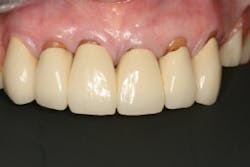

In this case, the diagnostic wax-up of the mounted models gave the technician the new position of the upper incisal edge. The technician then set the maxillary teeth appropriately using models and additional photographs. At the same time, tooth No. 20 was restored, but the lab technician kept the crown and lower partial to predictably create the lower occlusal plane and easily articulate this with the upper immediate denture (figure 18). Note the improved curve of Spee in Figures 19 and 20. Upon completion of the prosthesis, treatment was completed as outlined and the results made the patient feel very comfortable functionally, esthetically, and phonetically.

There was some fine-tuning to the patient's occlusion during the healing period. Nevertheless, the goals of treatment were accomplished very predictably. Figures 21 (horizontal position) and 22 (vertical position) verify both the new vertical and horizontal positions of the upper incisal edge.

Understanding the patient’s masticatory system requires the dentist to gather the correct data through a comprehensive examination. (6) In addition, diagnostic records (mounted models in centric relation and digital photography) can be used to provide predictable results. The overall esthetic outcome, along with improved function, gave the patient a new outlook on life and increased confidence—all within her budget (figures 23–25). The Dawson Academy is a great resource for learning about the masticatory system, functional esthetics, and a predictable treatment-planning protocol.